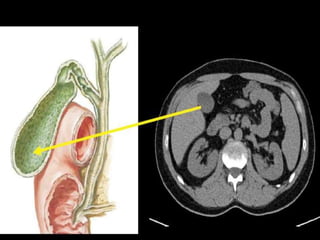

MR Angiography.

Right pelvic renal transplant

as seen on MRA.

MR Angiography. Right pelvicrenal transplant as seen on MRA.